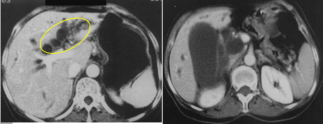

CT表现:平扫呈单发或多发圆形高密度影;肝内胆管结石:常为高密度,呈与肝内胆管走行一致的结节状影,常伴有周围胆道扩张;胆总管结石:多为高密度。结石上部胆管扩张。可见“环靶”征或“半月”征。

MRI表现:与结石成分有关:T2WI,高信号胆囊内可清楚显示低信号结石;胆管结石在T2WIMRCP上呈低信号,MRCP能显示梗阻上方胆管扩张程度,扩张胆管下端呈杯口状充盈缺损。

3胆囊癌CT表现:胆囊壁不均匀增厚、腔内乳头状结节影;基底部胆囊壁增厚;胆囊区不规则软组织肿块影;增强扫描,肿瘤及其局部胆囊壁常明显强化。

4胆管癌CT/MRI影像表现肝门胆管癌:多可在肝门区发现软组织结节或肿块,肝内胆管扩张中段和下段胆管癌:肝内和近段胆管扩张明显,胆管扩张突然变小或中断,局部胆管壁增厚或可见软组织结节或肿块,增强扫描明显不均匀强化